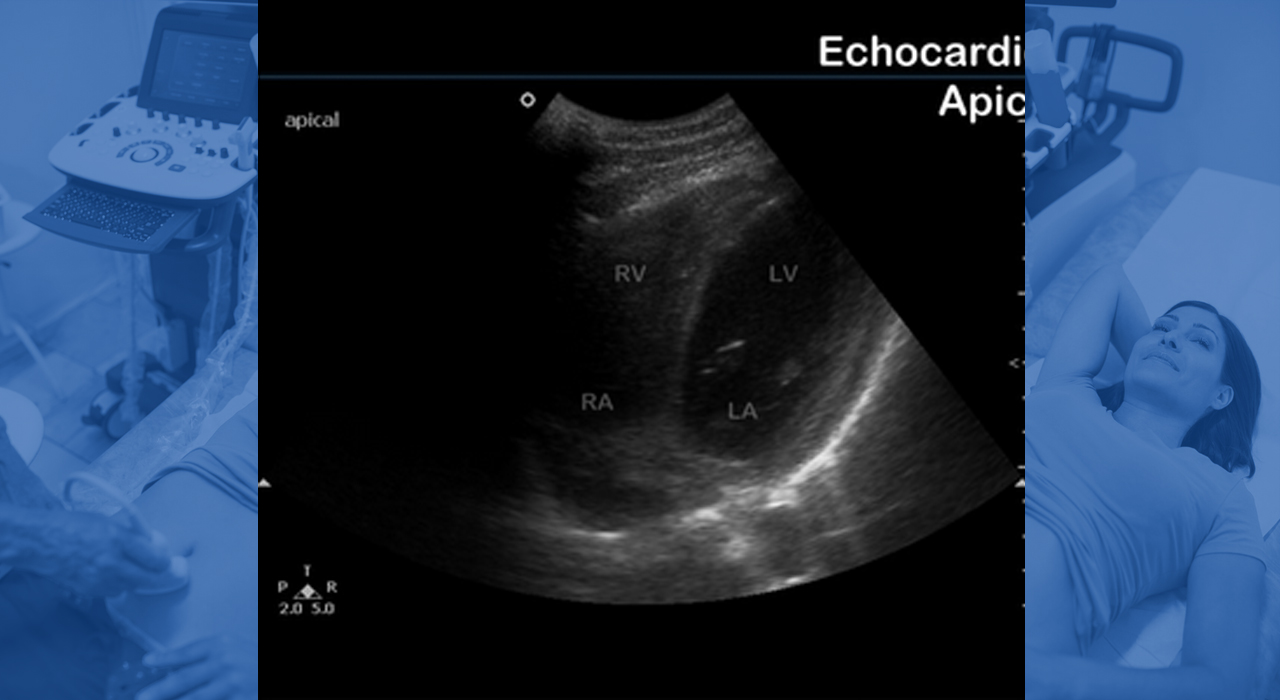

• CARDIACO

CARDIACO

Desde valorar rápidamente la fracción de eyección y trastornos de motilidad, hasta ver la presencia de derrame pericárdico o valvulopatías.

Con múltiples vistas, el clínico puede establecer una buena correlación clínica de lo observado con lo presentado por el paciente y así tomar decisiones rápidamente.

• Gran uso para diferenciar causas de disnea e incluso corroborar ausencia de neumotórax en situaciones de emergencia.